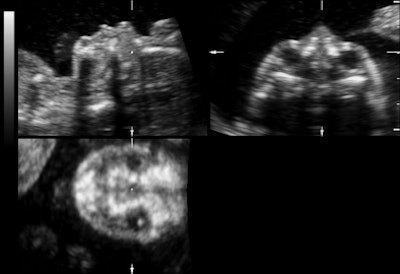

| Representative fetal profile images showing good-quality (above), acceptable-quality (below), and poor-quality (bottom) images. All images courtesy of the Journal of Ultrasound in Medicine. |

![]() |